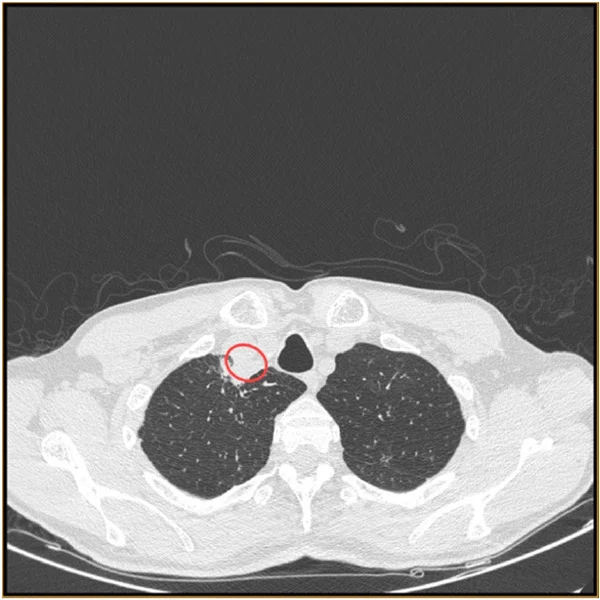

2023年6月發表的一項病例研究描述了印度東部地區的一名男性患者,他出現咳嗽、嗓音嘶啞、疲勞和吞嚥困難的症狀。他的頸部進行了CT掃描和X光掃描,發現氣管旁邊有一個充滿膿液的膿腫。